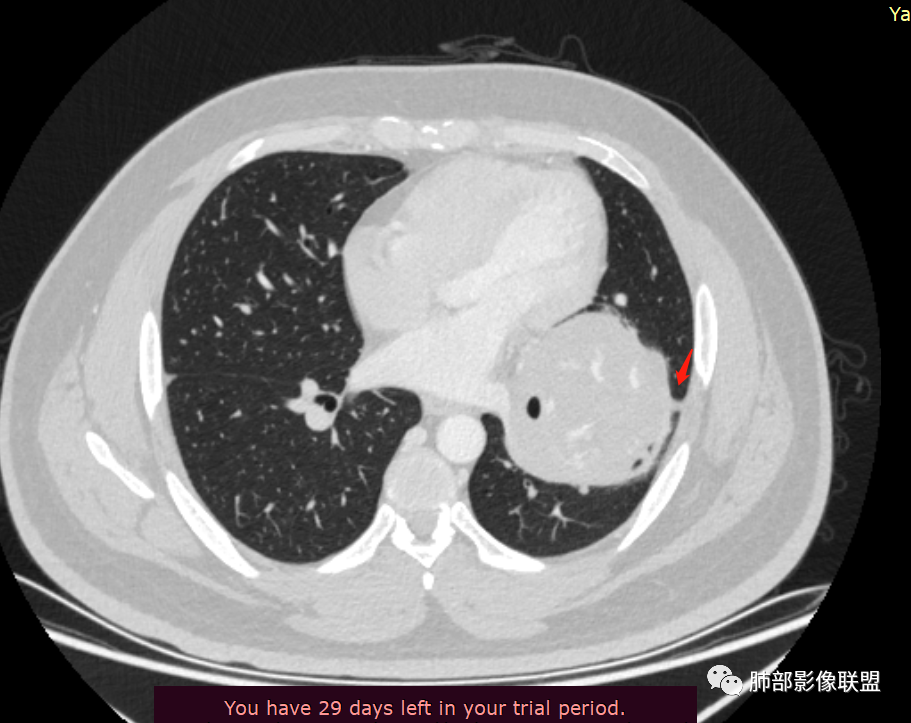

下肺静脉:

还是肺动脉供血,肺静脉引流

青年男性,体检发现左肺不规则类圆形占位性病变,叶间裂区域,定位胸膜来源。左肺下叶支气管受压狭窄,但管壁光整,未见腔内阻塞或管壁受侵。包块边界清晰,浅分叶,内部密度不均匀,病灶后份见空气新月征。渐进性强化,增强动脉期见分支状血管,蛇纹血管征。肺门纵膈未见增大淋巴结,符合孤立性纤维瘤(SFT)。

5)肿瘤的强化程度及方式:增强扫描肿瘤早期实性成分呈不均匀斑片或斑驳样强化,亦可呈“ 地图样” 明显强化,强化程度不一,可呈轻度-显著强化;静脉期持续强化,多期增强及动态增强扫描均呈“快进慢出”型强化,且强化范围逐渐增大并趋均匀。肿瘤内部及周围常见多发粗细不等强化或流空肿瘤血管影。瘤体内“蛇纹血管”在其他诸如硬化性肺细胞瘤、错构瘤等等是非常罕见的。